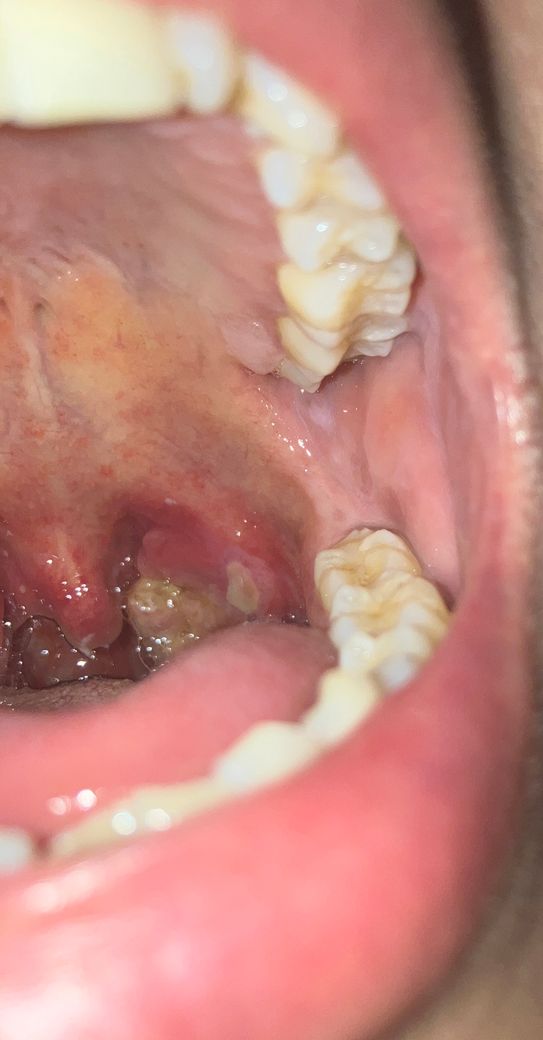

인후두염인거 같은데 병원에 가면 무슨 조치가 될까요

어느날 하루 무리를 해서 그런가 구내염에 쎄게 왔는데 상태는 이렇구요 현재 침삼킬때마다 약간 통증이 있습니다

현재 약국에서 치료형 가글 알약 알보칠 한번씩 바기 를 하면서 집에서 최대한 조치하고 있는데 병원에 가면 이런 약 처방 말고 해주실수있는게 있을까요..

• 2번 째 사진

말씀하신 것처럼 알보칠을 통한 치료 효과를 기대해 볼 수 있겠지만, 자세한 원인 확인을 위해서 사진 상의 병변 부위에 대한 배양검사를 진행하여 특정 세균이 검출되면 항생제 치료를 통해 치료 기간을 단축시킬 수 있습니다. 항생제의 경우 병원에서 처방이 필요한 약제로 진찰 후에 처방받을 수 있습니다.